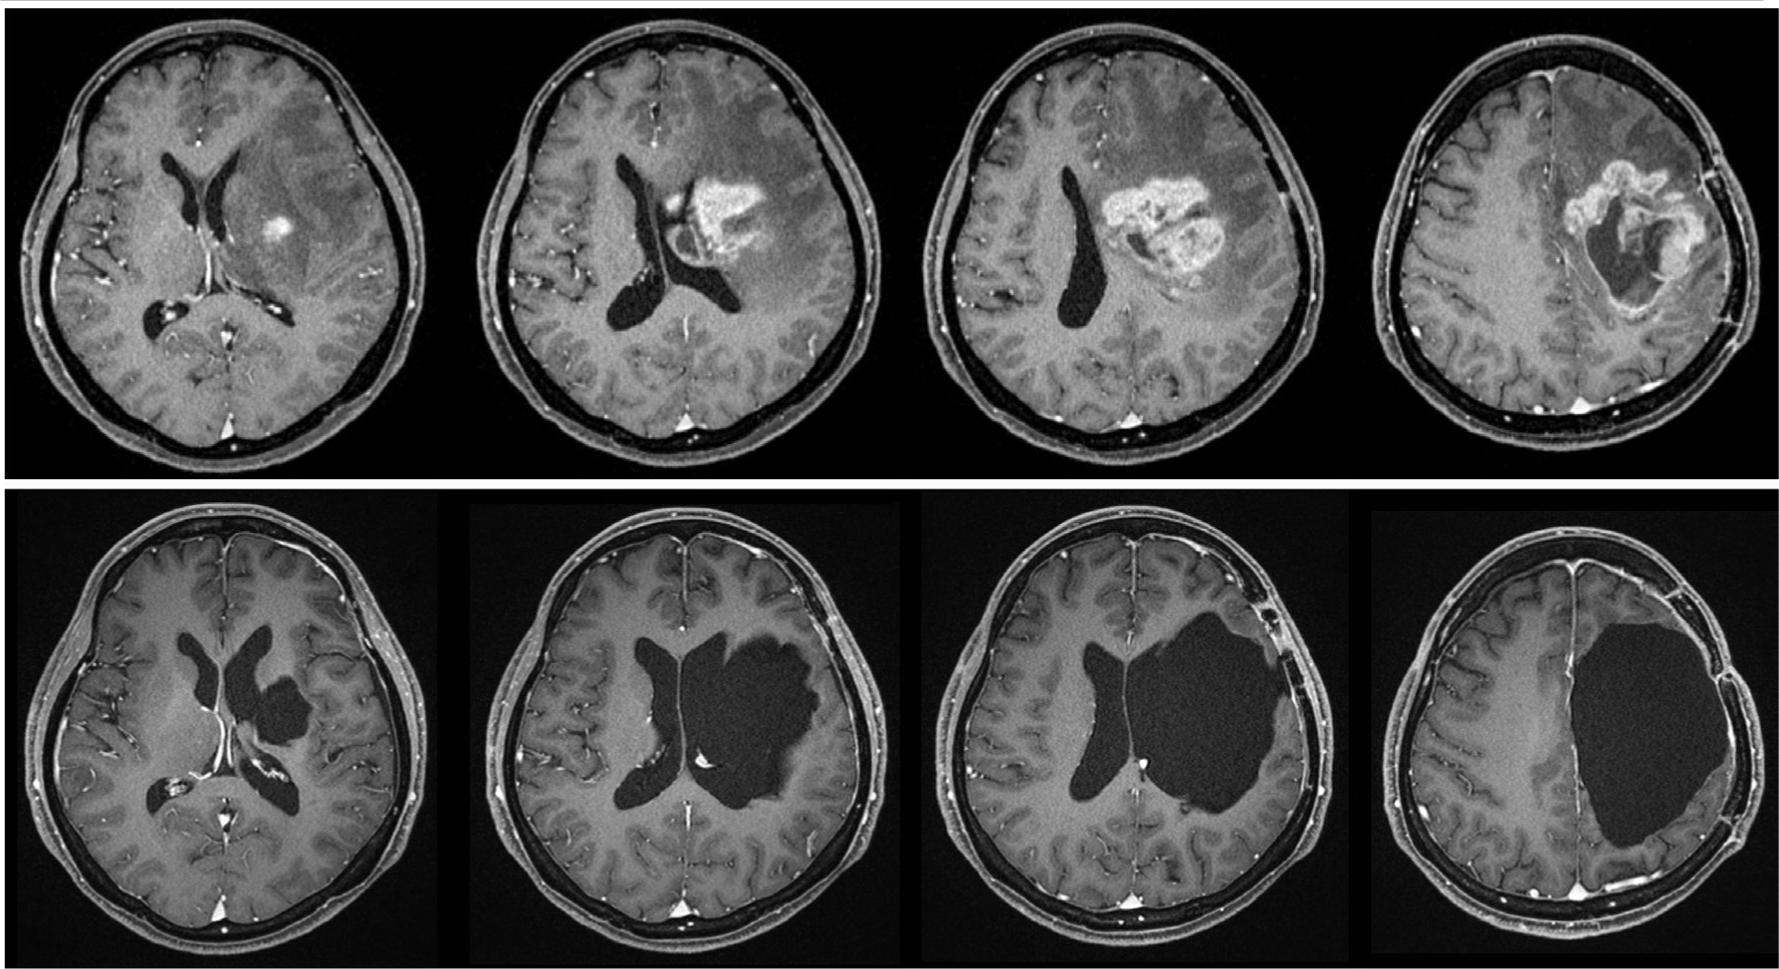

Four months later, the tumor rapidly extended to the pyramidal tract, basal ganglia and corpus callosum four months after the fourth surgery (Figure 3, upper). She had mild motor aphasia and right hemiparesis: proximal U/E MMT 2, distal U/E MMT 4, lower extremity (L/E) MMT 2. Her Karnofsky performance state score was 70%.

MRI before fifth operation revealing that the enhanced lesion invades to the basal ganglia, left lateral ventricle, splenium, and internal capsule (upper). Postoperative MRI revealing that the enhanced lesion totally disappears.

A fifth surgery was planned. A decision for radical tumor resection together with the surrounding structures was made. The patient and her family consented for postoperative right hemiplegia following surgery in order to improve her chance of survival. Fortunately, her right hemiparesis did not deteriorate after surgery and she could ambulate by herself with a cane, but motor aphasia slightly worsened (video is available). Several radiological investigations were checked after radical removal surgery. An MRI confirmed that the extent of resection extended to the superior and middle frontal gyri, anterior parietal gyrus, cingulate gyrus, corpus callosum, centrum semiovale, coronal radiation, basal ganglia and internal capsule (Figure 3, lower). The MRI tractography, of which the seeding point was placed at the cerebral peduncle, revealed that the pyramidal tract was not demonstrated at all; only fronto-pontine tract and temporo-pontine tract were demonstrated. Functional MRI by the task of right L/E movement (knee extension and flexion) revealed that the hot spot appeared in the left cerebellum and right motor area (Figure 4). However, several hot spots also appeared in the removal cavity suggesting artefact contamination caused by the rough L/E movement task.

MRI after fifth operation. Tractography in which the seeding point is placed at the cerebral peduncle, showing only fronto-pontine tract and temporo-pontine tract (upper). Functional MRI by the task of right knee extension and flexion showing the hot spot not only in the left cerebellum and right motor area but also in removal cavity.